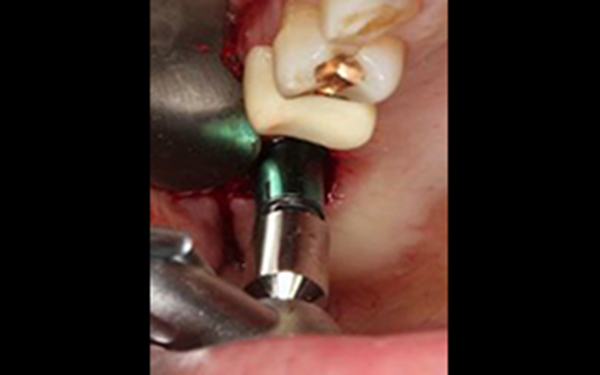

植牙合併無敲擊水壓式上頷竇增高術